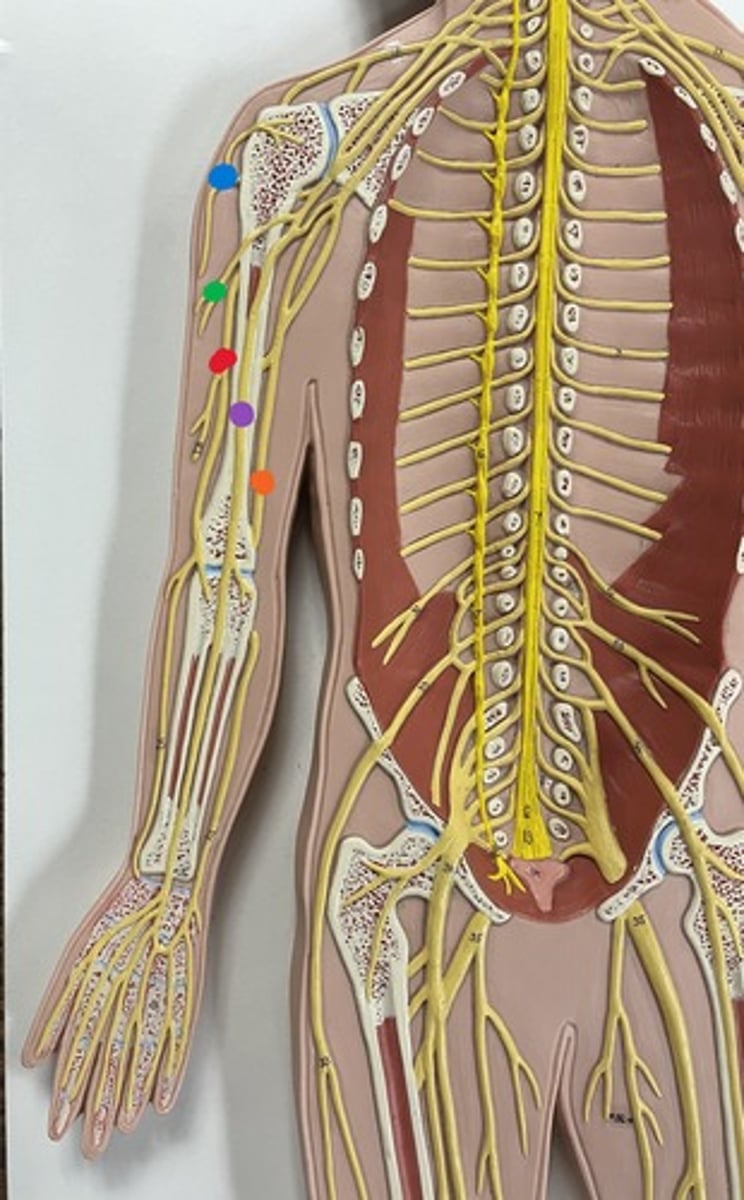

Brachial plexus

Axillary nerve

blue

Musculocutaneous nerve

green

Median nerve

purple

Ulnar nerve

orange

Radial nerve

red